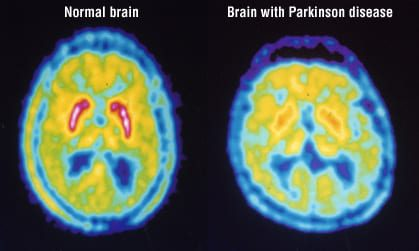

Positron Emission Tomography (PET)

involves injecting a radioactive tracer into the bloodstream, which emits positrons.

detected to create images of brain activity based on glucose metabolism or other markers.